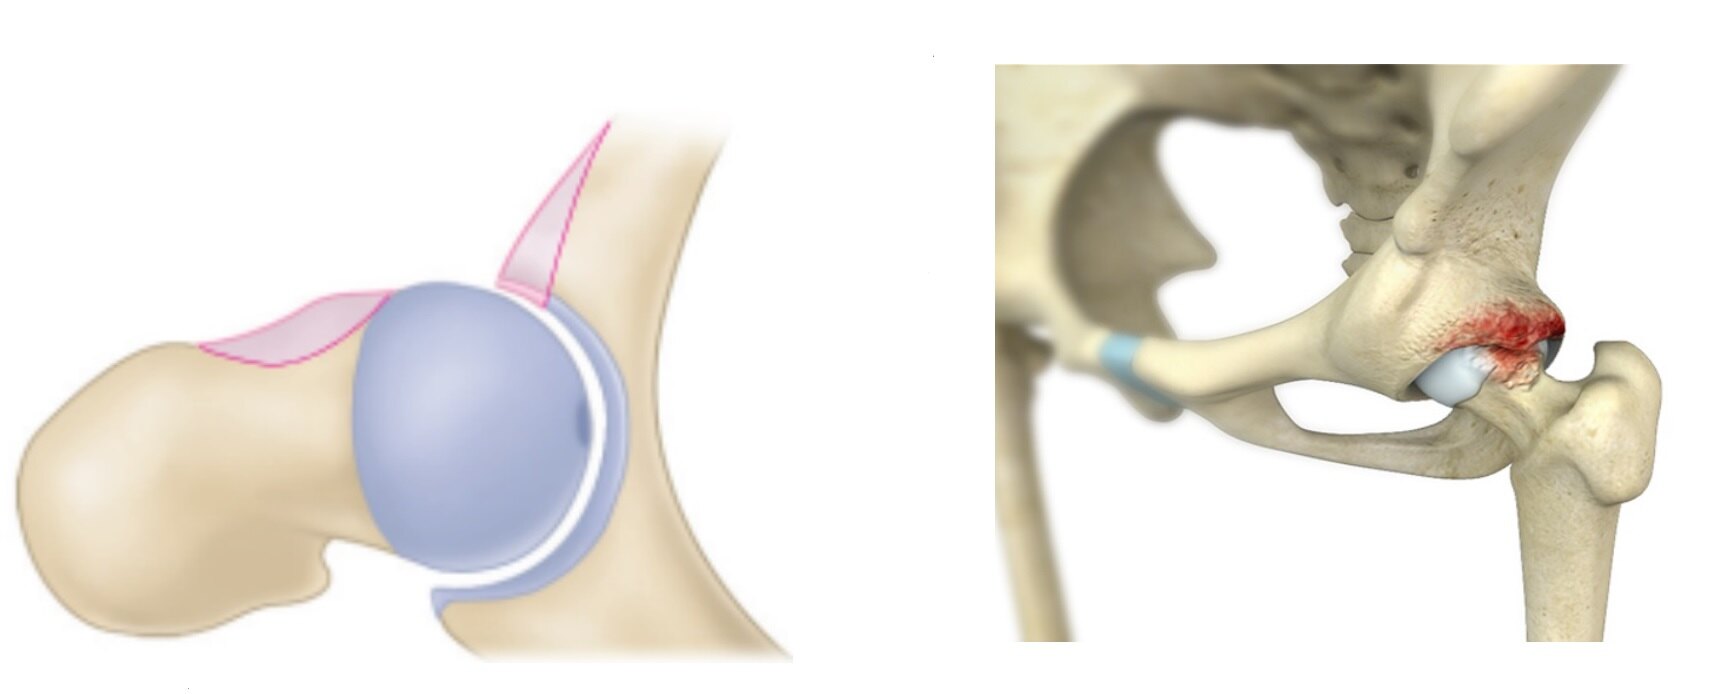

(2) 髋关节盂唇损伤:髋关节周围“C”形区疼痛、活动受限。

盂唇(labrum)附着于髋臼缘,像一个“皮搋[chuāi]子(马桶疏通器)”,在关节内少量关节液形成负压的条件下,可以吸住股骨头,防止股骨头脱位。

盂唇感觉神经分布丰富,髋关节撞击损伤盂唇,导致髋关节周围“C”形区疼痛,髋关节活动受限。

图9.髋关节撞击主要损伤的是髋臼缘的“盂唇”,因富含神经纤维的盂唇受损,出现髋关节周围疼痛。